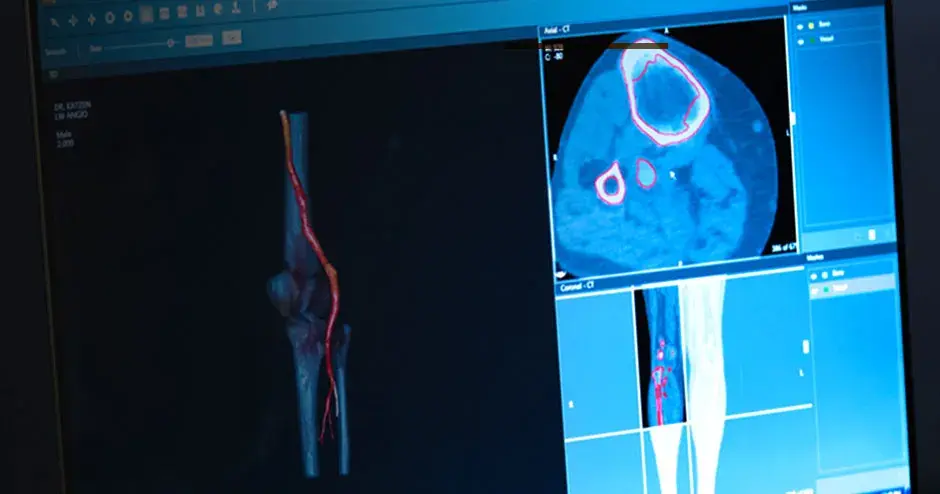

The ability to print patient-specific instruments and devices on demand and on-site is revolutionizing healthcare. By bringing 3D printing and procedural planning technologies to the point-of-care, healthcare providers are improving outcomes1, 2, increasing efficiency4, and lowering the cost of care5. Additionally, hospital operations are discovering that additive manufacturing can help fill supply chain gaps, enabling the production of needed medical supplies on demand.

Craniomaxillofacial, orthopaedics and radiation oncology are just a few of the specialties in which 3D printing at the point-of-care can expedite patient-specific procedures. Applications include: